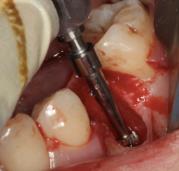

诊断:35牙牙松动。 治疗:拔除患牙,即刻种植。 手术记录:常规消毒铺单,局部浸润麻醉,于35牙牙位行横行切口,骨膜剥离器剥开黏骨膜瓣,显露术野。拔除松动牙,生理盐水冲洗冷却下,球钻定位,植入种植体,旋入愈合帽。 术后拍片,种植体方向好。10天后检查,伤口初步愈合。